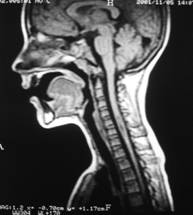

Īn stare de repaus protonii de H din corpul omenesc sunt orientati anarhic. Daca īi supunem unui cāmp magnetic static intens care actioneaza din afara corpului la o temperatura joasa, ei se aliniaza cu axul lor paralel sau antiparalel cu directia cāmpului magnetic. Sub actiunea unui alt cāmp exterior protonii īsi pierd orientarea si alinierea revenind la pozitia lor initiala de echilibru, trec printr-o faza de tangaj care consta īntr-o miscare de rotatie analoga miscarii unui titirez īn timpul careia emit un semnal de rezonanta receptionat de bobinele detectoare. Amplitudinea semnalului receptionat este proportionala cu numarul de nuclei din proba. Protonii de H care se vad mai bine sunt cei legati de apa si grasimi. Aceste doua medii dense īn protoni apar albe, osul (15 % apa) apare negru ca si plamānul. Fluidele īn miscare avānd protonii īn miscare au semnale foarte slabe.(jos-imagini rezonanta magnetica-abdomen, respectiv coloana cervicala)